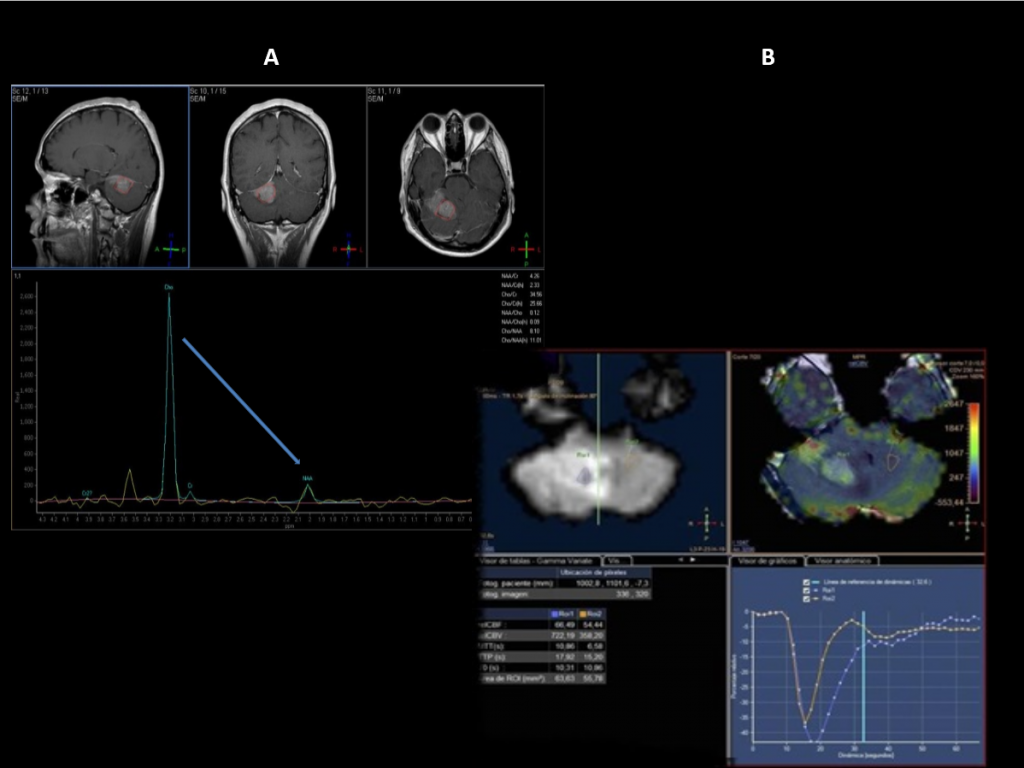

FIGURA2:

Espectroscopia: patrón maligno con marcado aumento de la colina y descenso del NAA

Estudio de perfusión:  la lesión presenta aumento del volumen sanguíneo cerebral más de dos veces respecto a la sustancia blanca contralateral